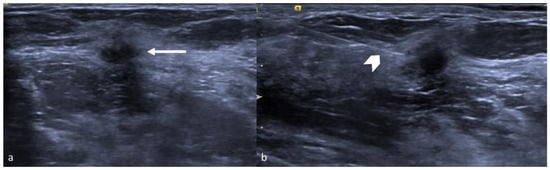

7. Radiofrequency Identification Tags